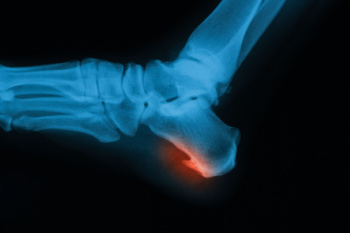

Heel spur surgery is considered when a bony growth on the heel bone continues to cause pain despite other forms of care. These spurs form when repeated strain on the foot leads to calcium buildup along the bottom or back of the heel bone, or calcaneus. Although not all heel spurs cause pain, in some cases they can create pressure and irritation with each step. Surgery removes the excess bone and reduces tension on nearby tissues, including the plantar fascia on the sole of the foot or the Achilles tendon at the back of the ankle. A podiatrist will examine the source of the pain, review imaging, and decide whether the spur on the bottom of the heel or near the tendon attachment needs to be removed. Recovery takes time as the foot heals and strength returns. If you have developed a heel spur that is causing pain, it is suggested that you make an appointment with a podiatrist for a diagnosis and treatment.

Heel spurs are formed by calcium deposits on the back of the foot where the heel is. This can also be caused by small fragments of bone breaking off one section of the foot, attaching onto the back of the foot. Heel spurs can also be bone growth on the back of the foot and may grow in the direction of the arch of the foot.

Older individuals usually suffer from heel spurs and pain sometimes intensifies with age. One of the main condition's spurs are related to is plantar fasciitis.

The pain associated with spurs is often because of weight placed on the feet. When someone is walking, their entire weight is concentrated on the feet. Bone spurs then have the tendency to affect other bones and tissues around the foot. As the pain continues, the feet will become tender and sensitive over time.